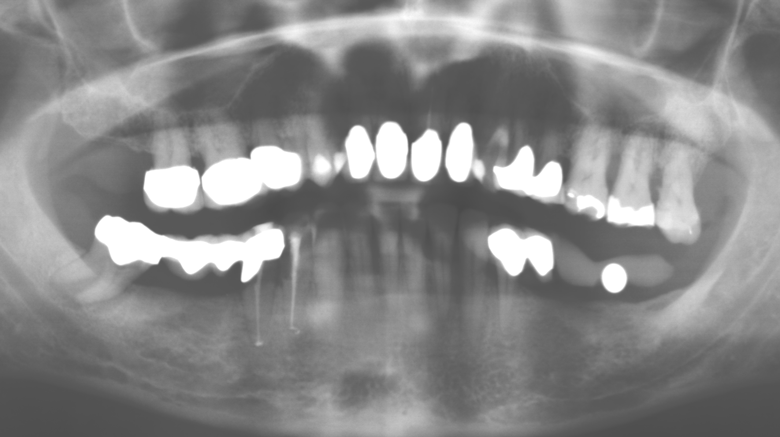

Abb. 1: Panoramaschichtaufnahme des Ausgangsbefundes im Jahr 2004.

Eine 52­-jährige Patientin stellte sich nach Zahnverlust im 3. Quadranten erstmals 2004 vor. Sie hatte den Wunsch nach einer prothetischen Neuversorgung. Im Rahmen der parodontologischen und radiologischen Diagnostik zeigte sich ein ausgeprägter parodontologischer Behandlungsbedarf. Die Zähne 48, 28, 27 zeigten zudem eine infauste Prognose und wurden entfernt (Abb. 1). Nach der erfolgreich abgeschlossenen systematischen PAR­Therapie wurde eine festsitzende implantatprothetische Versorgung mit Insertion von fünf Implantaten in Regio 35, 36, 37 und 46, 47 durchgeführt. Die prothetische Versorgung der natürlichen Zähne erfolgte mit verblendeten Zirkonoxidkeramikkronen, die Implantate wurden mit zweiteiligen individuellen Zirkonoxidabutments und ebenfalls verblendeten Kronen aus einer Zirkonoxidkeramik versorgt (Cercon base colored, Dentsply Sirona Lab). Die definitive Insertion der prothetischen Versorgung erfolgte im Jahr 2005.